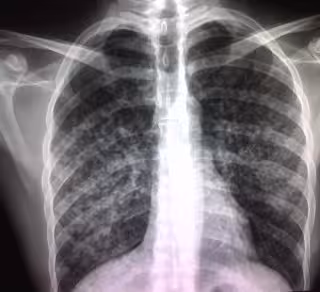

Tuberculosis

Foto: SANDRA BERMÚDEZ/ FLICKR